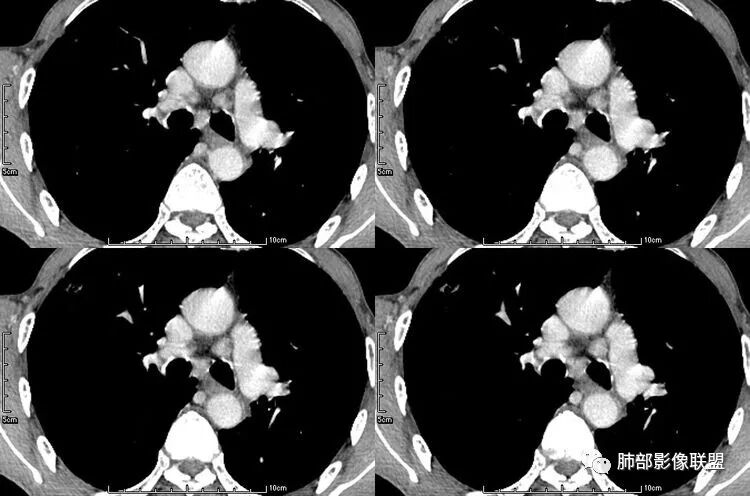

患者老年男性,咳嗽、咳痰、痰中带血伴胸闷2月余。长期大量吸烟史。查肝肾功能、血糖、血脂、心肌酶、电解质、血沉、C反应蛋白、抗“O”、类风湿因子、抗核抗体谱无明显异常。肿瘤标志物提示NSE、CYFRA21-1稍升高。胸部CT:肺气肿背景,左肺下叶后基底段不规则肿块影,见支气管截断,内见大片状低密度区及部分血管影,增强轻度强化,远端空洞形成。双肺多发不规则实性结节影、见毛刺、胸膜牵拉及血管集束,结节内见空洞形成,部分可见血管影,多位于胸膜下。双肺见多发肺大泡。综合考虑左下肺恶性病变并双肺转移。鳞癌或淋巴瘤可能。鉴别血管炎性病变及真菌感染。

左肺下叶团块病灶,有明显张力,增强后病灶内部有可疑延迟强化,看不清楚病灶与支气管的关系,应该支气管受压阻塞了,双肺多发胸膜下小结节,病灶小结节病灶有平行胸膜生长的表现,部分小结节厚壁,部分薄壁,,还有一部分有内容物,这需要两元论,左肺下叶肺癌(腺癌)伴转移,同时合并真菌感染。

张小兵:与血管关系密切

三个石头:都有血管从凹陷处进入

张玉:收缩,牵拉,血管增粗,与血管相连

无发热,其他慢性细菌先不考虑,有的低毒的,但是结节形态还是比较不规则的,分布也是比较随机,更像原发病灶。真菌方面,结节没有融合,坏死也是液化坏死,不符合隐球菌,曲霉不符合IPA,慢性吸入的也少见。结核没有树丫,不考虑。鉴别主要是GPA,和肺癌。GPA不支持点是皮肤,肾脏没有累及,ANCA不支持。。。肺癌主要是腺癌和鳞癌转移。比较支持的是淋巴结肿大,和左下肺的主病灶,支气管堵塞和异常强化。还有分叶,局部膨隆。可以建议支气管镜检测。

本病例左肺下叶肿块,有深分叶、毛刺、胸膜牵拉凹陷、支气管截断及纵隔内淋巴结肿大等征象,都均支持病灶为恶性,如腺癌,而且叶间裂的多发结节也提示是腺癌来源可能大;双肺多发结节、肿块,大部分病灶有分叶、毛刺及胸膜凹陷的恶性征象,与原发肿瘤本身的性质有关,所以应该与左肺下叶肿块同源,而且双肺多发病灶内空洞也具有多样性;